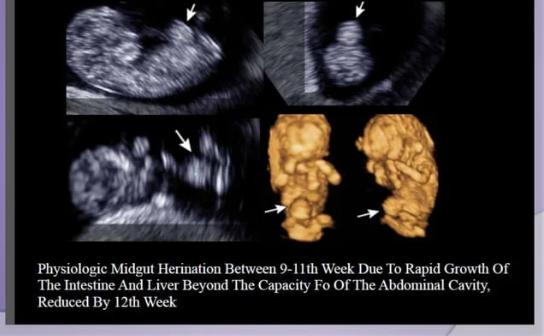

Professor, Division of Interventional Radiology Special interests: Angiography, fetal imaging, and interventions Co-investigator for ICMR study – National Registry on Venous Thromboembolic Disorder, RGGGH TAEI coordinator.